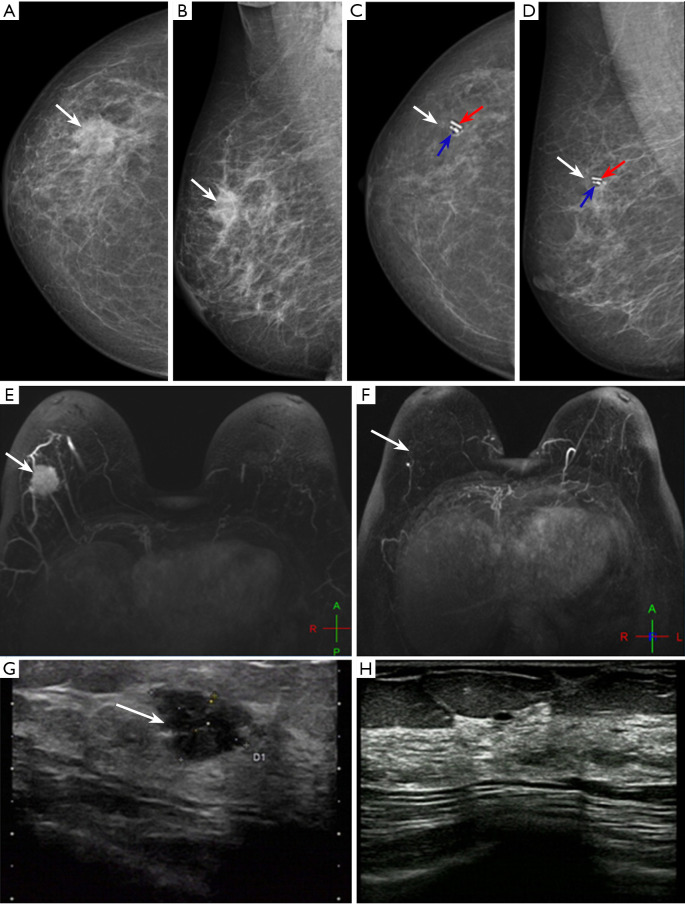

Methods: From October 2022 to October 2024, a prospective single-arm study was conducted on 132 patients with primary breast cancer who achieved breast radiologic complete response (brCR) or breast radiologic partial response (brPR) after NAT at the Breast Center of Shandong Cancer Hospital. Before NAT, a marker clip was placed at the center of the tumor bed. After NAT, in patients with no residual lesions suggested by ultrasound, iodine-125 was placed under the guidance of mammography, followed by routine breast surgery (breast-conserving surgery or mastectomy). Postoperatively, multiple-site core needle biopsy (CNB) under ultrasound guidance was performed on the surgical specimen. The pathological results of CNB specimens were compared with those of surgical specimens to assess the accuracy of CNB in predicting bpCR (ypT0) after NAT.

Results: A total of 52 patients (39.4%) achieved bpCR after NAT. Univariate analysis showed that tumor molecular subtypes, brCR after NAT, and axillary pathological complete response (apCR) were significantly associated with bpCR (P=0.02, 0.02, and P<0.001, respectively). Ultrasound-guided multiple-site CNB had an accuracy, negative predictive value (NPV), and false-negative rate (FNR) of 90.9%, 81.0%, and 14.8%, respectively, in predicting bpCR after NAT, which were superior to those of ultrasound, mammography, and magnetic resonance imaging. The combination of imaging examinations and ultrasound-guided multiple-site CNB significantly reduced the FNR compared with CNB alone (7.4% vs. 14.8%; P<0.001). No false-negative results were found in 45 cases using large-bore CNB needles (12G).